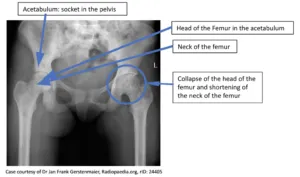

- Avascular necrosis (hip, shoulder), leg ulcers, priapism.

- Bone: Avascular necrosis (femoral/humeral head), osteomyelitis (📌 Salmonella > S. aureus).